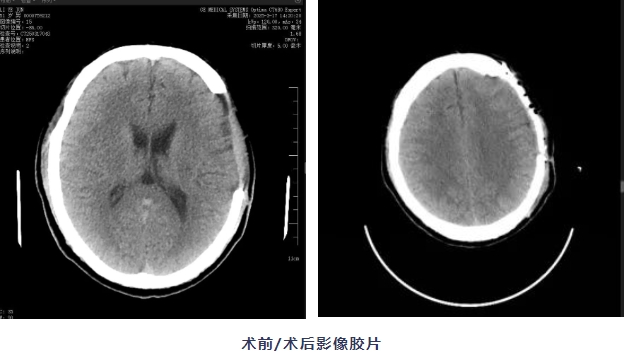

近日,我院神經(jīng)外科團隊為一名創(chuàng)傷性硬膜下血腫術(shù)后患者成功實施了一例特殊手術(shù)——PEEK顱骨修補術(shù),讓患者重新獲得完整頭型的同時,更幫助他找回正常生活的勇氣。

張師傅(化名)是一名建筑工人,3個月前,他在工地意外受傷,經(jīng)過緊急開顱手術(shù)保住了性命,但右腦側(cè)留下了一個凹陷。每次出門,張師傅都戴著帽子,又悶又熱不說,還經(jīng)常感到頭暈耳鳴,性格也變得孤僻。為恢復(fù)顱腔完整性,提升生活質(zhì)量,他于術(shù)后1月再次入院,我院專家會診評估后,擬行顱骨修補手術(shù)。

“患者的情況,就像手機少了保護殼,大腦缺少了防護。”神經(jīng)外科主任邱斌表示,傳統(tǒng)顱骨修補材料存在導(dǎo)熱性強、術(shù)后異物感明顯等問題,好比金屬板,冬天冰涼夏天發(fā)燙,還容易變形。本次手術(shù)擬采用的PEEK(聚醚醚酮,一種高級醫(yī)用塑料),具有高度生物相容性、精準(zhǔn)三維塑形、隔熱抗感染等優(yōu)勢,與人體骨骼彈性模量接近,可避免應(yīng)力性損傷,同時通過3D打印技術(shù)“量體裁衣”,制作出的"頭骨補丁"與患者頭型吻合。此外,該材料性能穩(wěn)定,可降低術(shù)后并發(fā)癥風(fēng)險。

在手麻科、放射科等多學(xué)科配合下,邱斌主任團隊?wèi){借豐富的顱腦手術(shù)經(jīng)驗,像拼樂高積木一樣,精準(zhǔn)將這個乳白色的"頭骨拼圖"嵌入缺損部位,術(shù)中出血少、操作時間短,顱骨外形自然對稱。